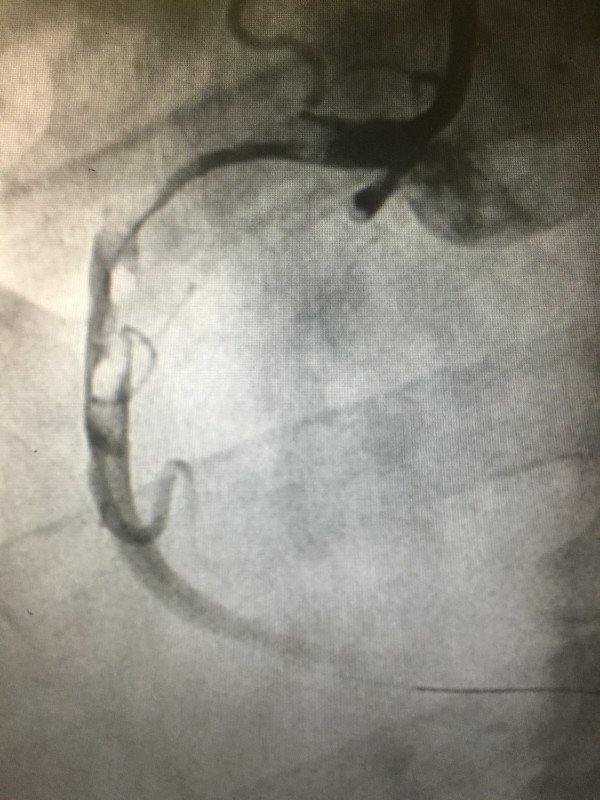

46 yaşında sigara kullanan hasta, gece yarısı ani başlayan göğüs ağrısı, bulantı, terleme, nabız ve tansiyon düşüklüğü şikayetleri ile acil olarak 112 tarafından kliniğimize getirildi. Yapılan acil anjigrafi sonucu kalbi besleyen sağ damarın tamamen tıkalı olduğu tesbit edildi. balon ve stent işleminden sonra tam açıklık sağlanarak hasta sağlıklı bir şekilde taburcu edildi